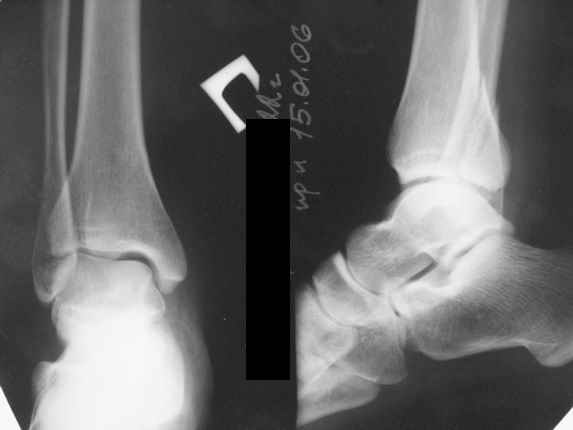

Тему неоднократно разбирали (см. архив), как всегда, недостаточны ренгенологические исследования - кроме прямого и боковых снимков, еще нужна косая ренгенограмма для определения ankle mortise, без мортиз снимка трудно определить высоту и ротацию малоберцовой. (снимки)

Ренгенология даст ответ как классифицировать перелом, на сегодня применяется классификация “Lauge Hansen fracture classification SER supination-external rotation или supination-eversion classification Danis

Weber А, В, С.”

Показания для фиксации: укорочения и ротация малоберцовой, особенно обращают внимание на любой подвывих таранной кости: неустраненый подвывих впоследствии приводит к раннему артрозу. Задний край фиксирует тогда, когда перелом составляет около 25% суставной поверхности голеностопного сочленения и смещение более 2мм.

По снимку ваш случай относится к Weber В, фиксацию производят восстановлением длины малоберцовой кости, под ренгеном (ЭП)контролем, для этого я предпочел бы латеральный доступ, остеотомия по линии перелома, удлинение малоберцовой засчет скоса линии остеотомии, компрессия “lag technique”по линии остеотомии и фиксацию провести латеральной пластиной. Отдельный задний доступ, остеотомия по линии перелома, репозиция и фиксация заднего края вашим предпочтительным методом: 3.5мм шурупом с шайбой или пластиной Antiglide Butress

method. При восстановленном суставе, уменьшится медиальная щель, а при Weber В повреждается только передне-нижняя межберцовая связка синдесмоза, повреждение которой приводит к наружной ротации

малоберцовой, но после восстановления всех смещений, связка автоматический приближается к исходному и нет необходимости восстановления синдесмоза.